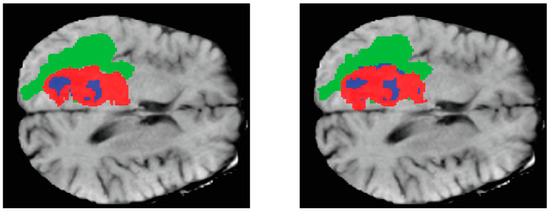

The representation of three-dimensional (3D) images on paper is often challenging, thus necessitating the display of the two-dimensional (2D) parts of these images. Figure 7 is an instance from the dataset, whereby three cuts have been made along the three axes of the image. The leftmost column displays the Flair channel images of the sample. The middle column exhibits the equivalent slices extracted from the real-state image. Lastly, the rightmost column portrays the amalgamation of the two columns, revealing three distinct tumor locations on the brain image, each represented by a different color, having undergone a transformation. The provided photos depict the inflamed region of the tumor in a green hue, the necrotic tissue of the tumor in a blue hue, and the actively proliferating core of the tumor in a red hue.

Figure 7.

Images of tumor swelling area with three different colors.

In this study, following the necessary preprocessing procedures specific to magnetic resonance imaging, the obtained data were utilized to generate image segmentation and classification. These outputs were subsequently employed as the input to a proposed network model, aiming to extract either a feature or category. Classifications are employed for categorization purposes. Several studies have demonstrated the potential impact of utilizing deep learning models in conjunction with neural imaging data [33,34]. Additionally, a group of researchers has presented a collection of brain tumor cases [25,29]. The findings presented by the experts indicate a notable enhancement in the classification outcomes. Consequently, it is anticipated that this study will contribute to the advancement of classification results in the domain of brain tumor detection and classification, employing diverse imaging data and deep learning models. Following the training of the proposed network on the majority of the BraTS dataset, we employed various data augmentation techniques to enrich the data and enhance the performance of the network. The subsequent sections will elaborate on the results obtained from these tests, while the final section will include a comparative analysis between the network’s highest accuracy and that of prior research. The initial network configuration is outlined in Table 1. Figure 8 and Figure 9 show a visual depiction of the network’s output and its corresponding steady-state image in three dimensions.

Figure 9.

Shows a two-dimensional cross-section of the brain image of one of the existing samples. In this figure, we can see the real status image next to the network output image, and the segmented areas of the brain tumor are marked with three colors. In this way, the swelling area of the tumor is shown in green, the dead tissue of the tumor is shown in blue, and the active core of the tumor is shown in red.